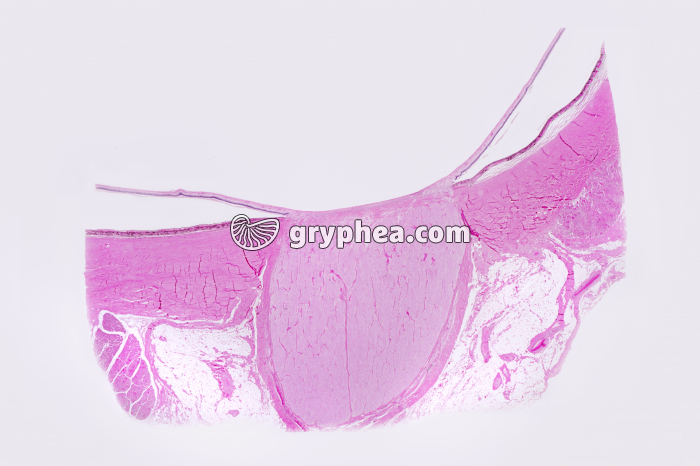

Tache aveugle Nerf optique x1,5

Tache aveugle Nerf optique x1,5 - gryphea.org